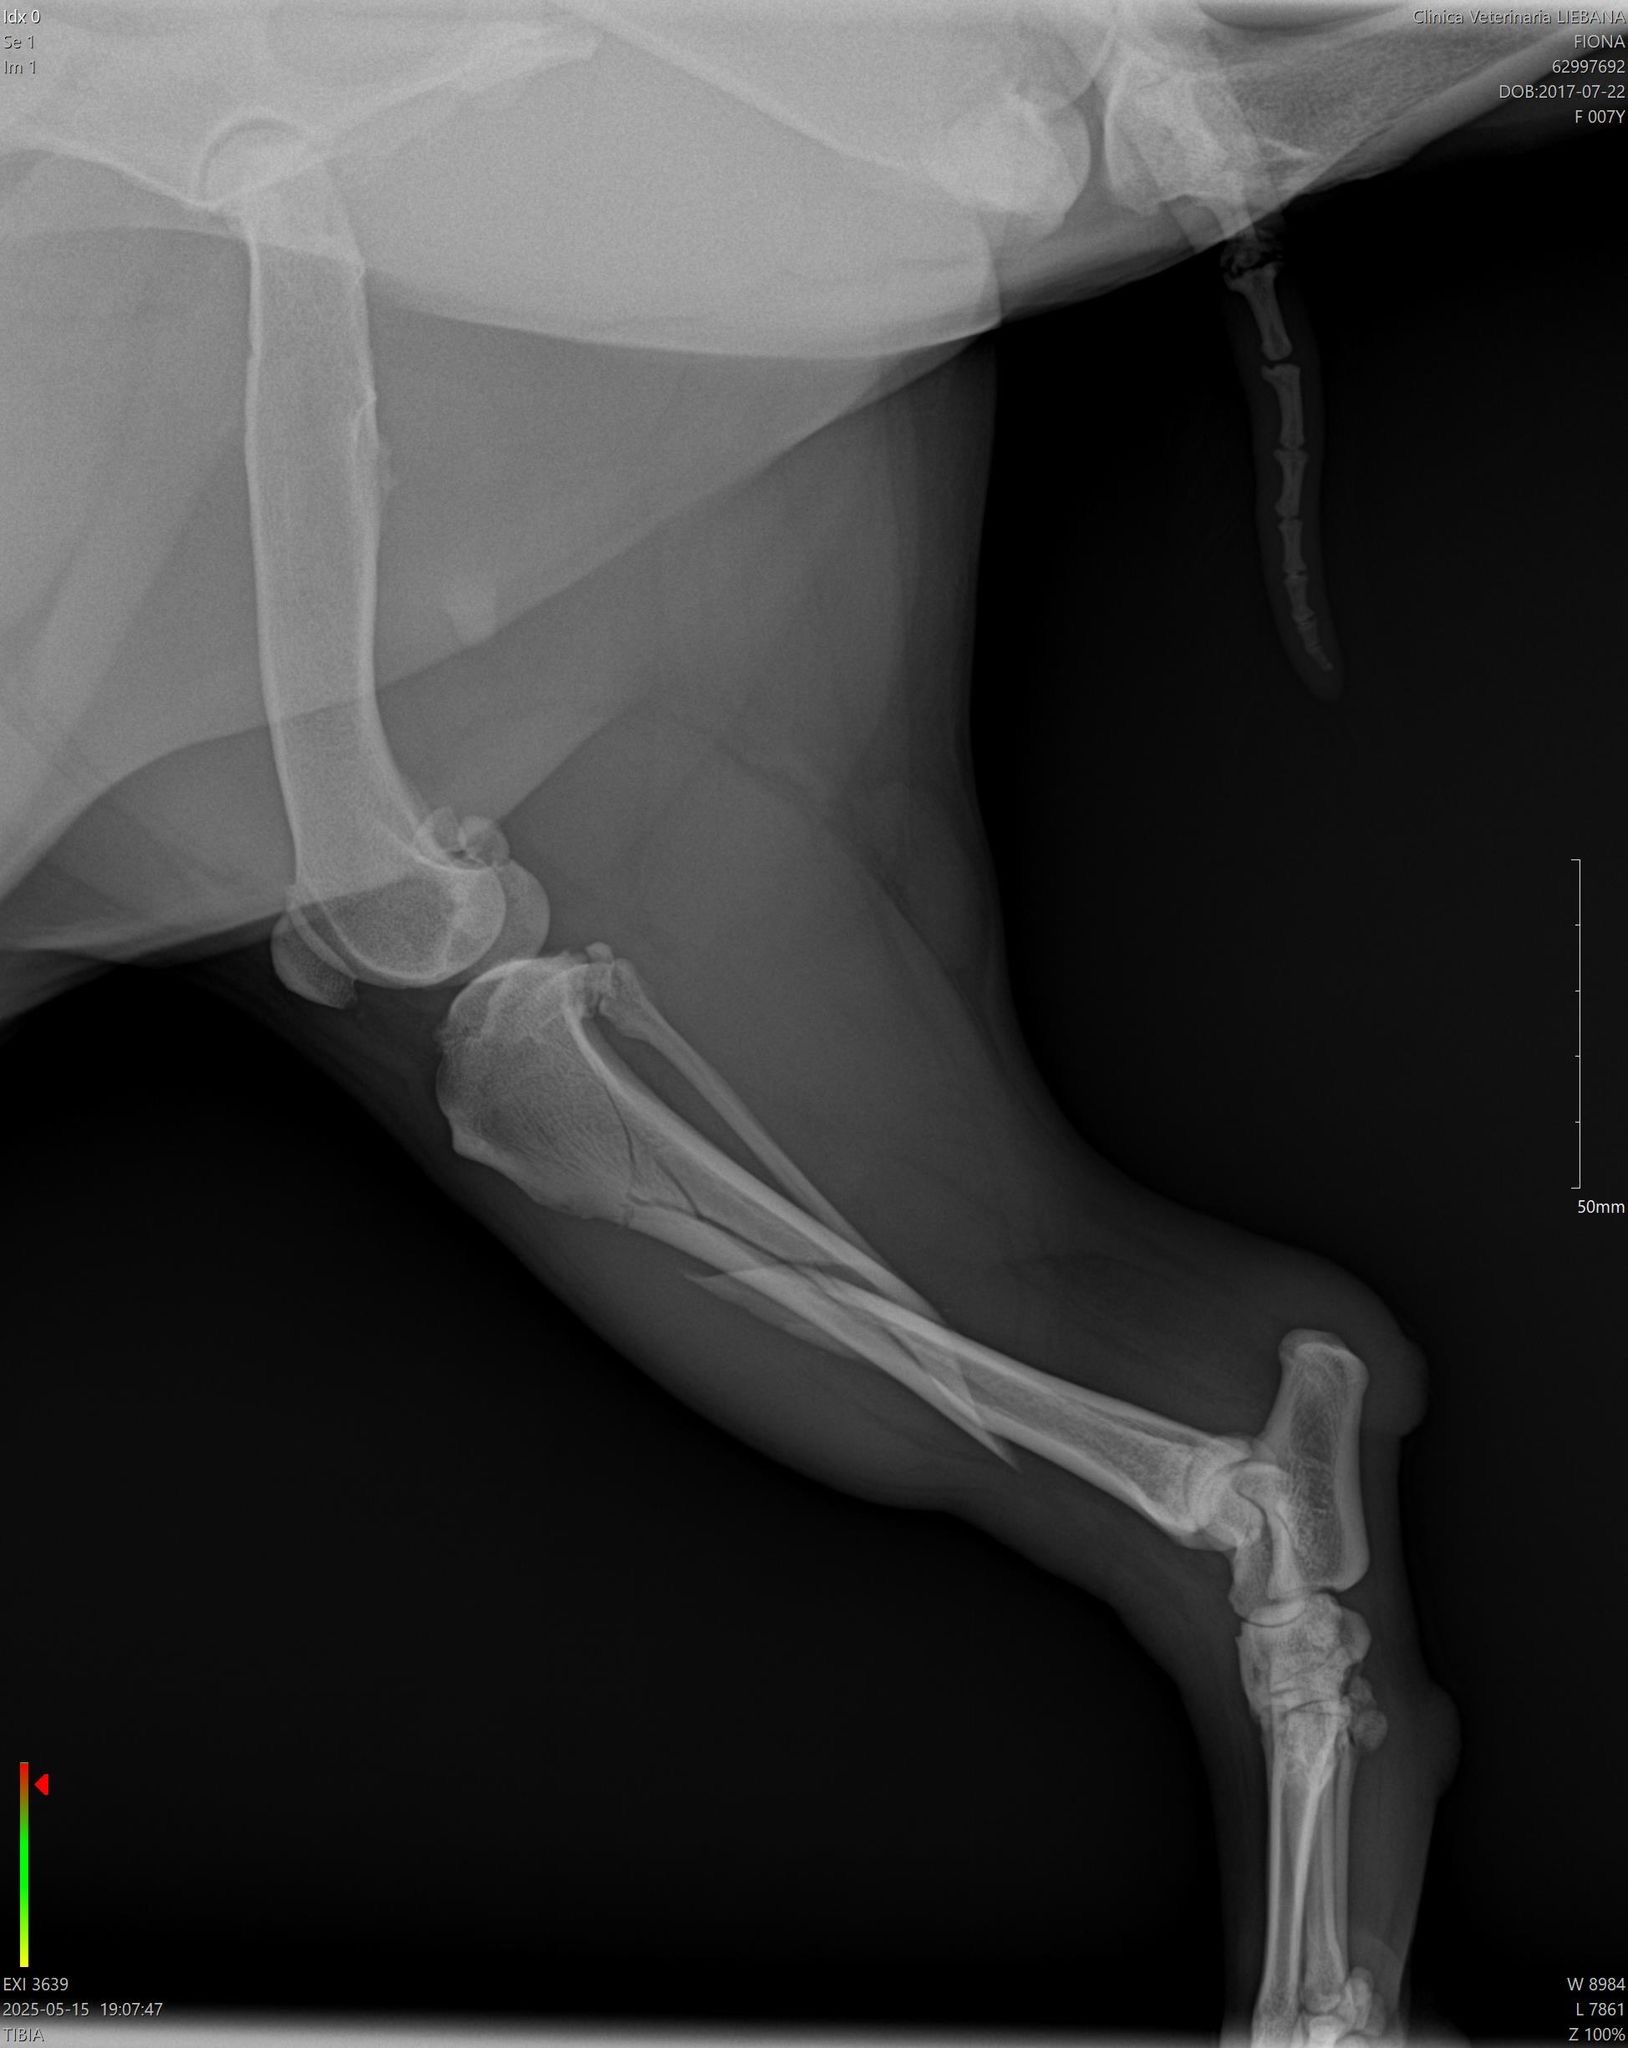

Hola, soy Fiona, soy una mini Bull terrier, tengo 7 años, soy muy cariñosa y sobretodo me gusta mucho jugar. La semana pasada, me rompí la patita, específicamente el fémur por lo que mi mamá me llevó al veterinario y le dijeron que era necesario hacerme una cirugía ya que con una escayola no podía repararse mi huesito.